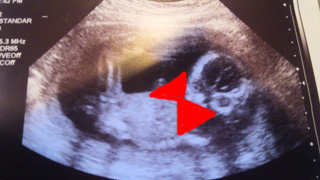

ハニコさんは、妊娠高血圧腎症になってしまった私のおなかでは育たず、

妊娠30周+0日を待ち未熟児医療を専門にする医療機関で、1440グラムの超低出生体重児で産まれました。

写真は、以前にも掲載したことがある3Dです。

少々エグイので、再アップ迷いましたが、

憎まれ口をたたき、反抗期のハニさんと向き合う今、大変だったころを思い出し、怒ってばかりじゃ

ダメだなと、初心に返る意味で。

ハニコさん、お誕生日おめでとうございます♪